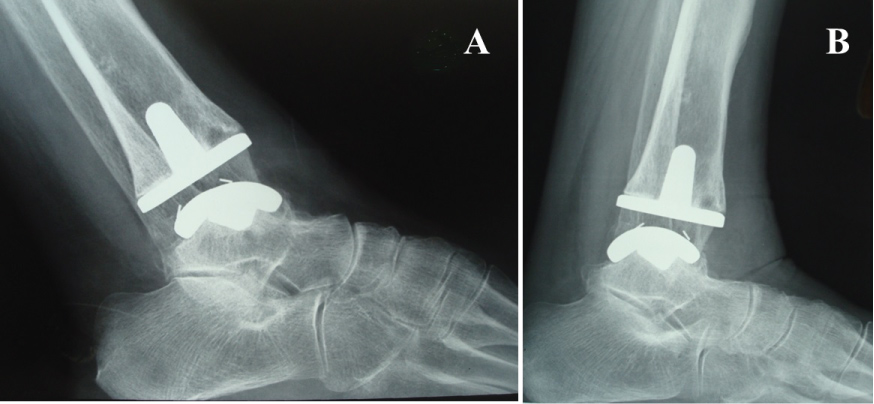

Lucencies were not seen in any of the zones around the talar component. Radiographs showed subsidence of the talar component < 5 mm in 3 ankles and a subsidence between 5 and 10 mm in 2 ankles (Figure 4). None of these 5 patients were associated with a clinical correlation in the radiographic finding. There were no cases of tibial component mobilization and migration. A periprosthetic asymptomatic cyst was detected in 1 patient with posttraumatic arthritis. The cyst was located in the medial zone [14] of the tibial component two years postoperatively (Figure 5). We observed a posterior osteophyte overhanging distally from the tibial plafond in 3 primary osteoarthritis ankles.

Figure 4: Radiographs showing subsidence of the talar component and radiolucency around the talar component. A) Lateral view; B) AP view. View Figure 4